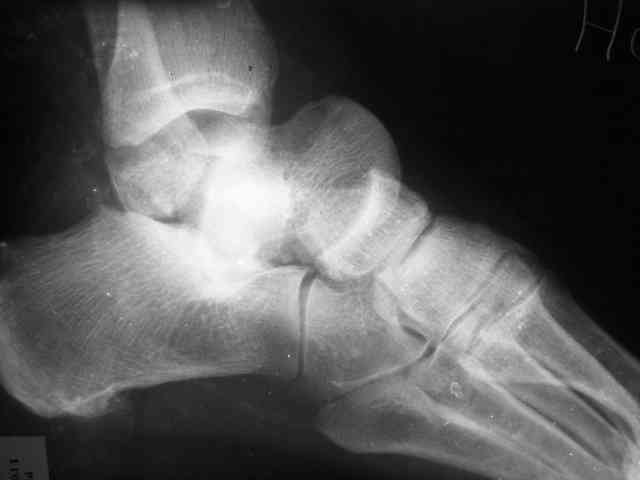

Уважаемый Александр! Как обещал представляю Р-граммы и операционные фото.

Последний снимок

Мнение по поводу тарана? АН есть?

> Мнение по поводу тарана? АН есть?

Типичная картина некроза.

На мой взгляд, у больного асептический некроз таранной кости, осложненный гнойным артритом голеностопного сустава (по снимку не понятно, что это - фистулография или простая рентгенограмма). Оптимален артродез голеностопного сустава, объем резекции таранной кости определится только интраоперационно. Большая проблема - метод фиксации. Работая, в основном, с пациентами пожилого и старческого возраста могу сказать, что ЧКОС они переносят плохо. Адекватный уход за аппаратом возможен только в условиях стационара. Возможность самостоятельной работы с аппаратом, например для ликвидации укорочения, крайне сомнительна. Кроме того, укорочение 3 см (до 5 см) у данной категории больных легче компенсировать ортопедической обувью. К сожалению и фиксирующие повязки (гипсовые и различные "касты")- не лучший вариант для пожилых людей (пролежни и флектены просто на "ровном месте"). В данном случае я бы применил простую "фиксирующею" компоновку аппарата Илизарова, с возможностью "отступления" к голеностопному брэйсу (тутору). Основная задача - максимальное восстановление самообслуживания больного и, по возможности, избежать "этапных" операций.